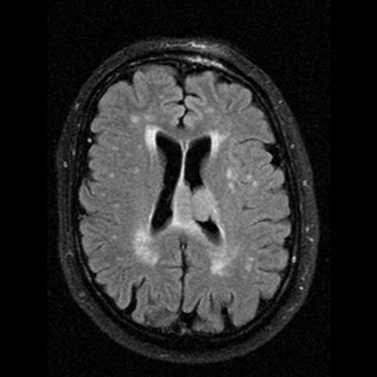

Multiple sclerosis typically appears with lesions presenting in the hemispheric white matter with a periventricular predilection. Other less usual locations for MS lesions include the cerebellum and the pons.

In the later stages the periventricular lesions can become confluent.

The method of choice for the imaging of multiple sclerosis is MRI. MS lesions secondary to their increased water content appear as increased signal intensity lesions on (T2 weighted), PD images and on FLAIR sequence.